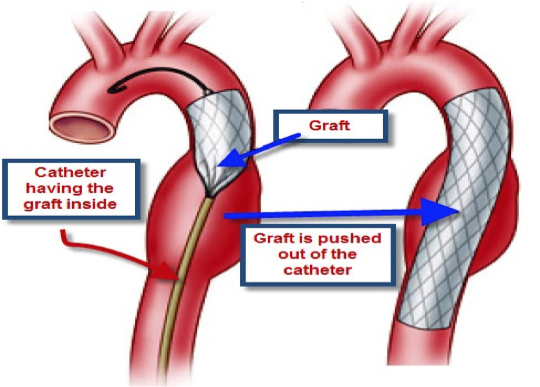

What does this refer to

Open surgical repair vs. endovascular

Endovascular repair

High risk of complications from open operations

Minimally invasive

Access usually through femoral arteries

Endovascular repair aortic aneursym